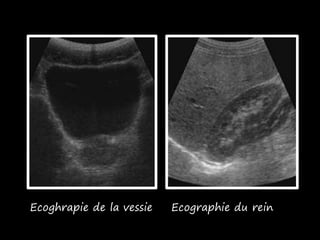

Ecoghrapie de la vessie Ecographie du rein

Ecoghrapie de lavessie Ecographie du rein